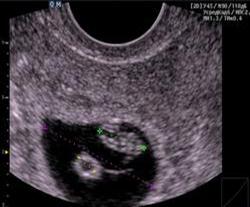

Рис.16. УЗИ органов брюшной полости